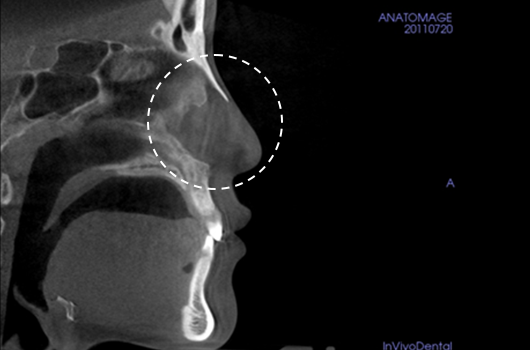

Operasi hidung CT 3D membantu pelaksanaan operasi hidung yang lebih canggih setelah menganalisis wajah secara cermat untuk menentukan mana yang terbaik.Analisis tiga dimensi digunakan untuk mengetahui keadaan secara umum, ukuran, bentuk, dan asimetri tulang hidung, tulang rawan septum hidung, dan jaringan kulit, yang tidak dapat ditentukan melalui konsultasi pada umumnya. Saat merencanakan revisi operasi hidung, kami dapat memeriksa elemen fungsional seperti deviasi septum hidung, bentuk implan yang ada, termasuk implan silikon, atau komplikasi dari operasi sebelumnya.

Pentingnya 3D-CT Scan pada Operasi Hidung

Dalam setiap konsultasi operasi hidung, Klinik Operasi Plastik Braun menggunakan 3D-CT scan untuk menganalisis isu-isu berikut dalam tiga dimensi: Rancangan bedah dapat dibuat lebih tepat dan potensi efek samping dapat berkurang dengan memahami lebih lanjut ukuran, bentuk, dan asimetri bagian hidung yang tak kasat mata dan struktur anatomi disekitarnya sebelum operasi.

1. Analisis tulang rawan septum dalam berbagai ukuran dan bentuk

2. Diagnosis dan tindakan untuk deviasi hidung dan deviasi septal

3. Analisis untuk lebar dan asimetri tulang hidung

4. Diagnosis Inferior turbinate asymametry dan pembedahan hidung tersumbat